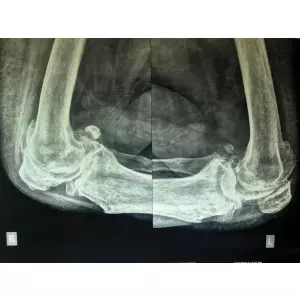

Dr. Samir Nanavati is one of the best orthopedic and joint or hip replacement surgeons in India. Knee replacement, also called knee arthroplasty, is a surgical procedure to resurface a knee damaged by arthritis. ... Continue

Dr. Samir Nanavati has, to his personal credit, performed more than 2500 orthopedic operations and 17+ years of experience in the field. Knee replacement surgery is a treatment for pain and disability in the knee.Knee replacement, also called knee arthroplasty or total knee replacement, is a surgical procedure to resurface a knee damaged by arthritis.The goal of knee replacement surgery is to resurface the parts of the knee joint that have be ... Continue